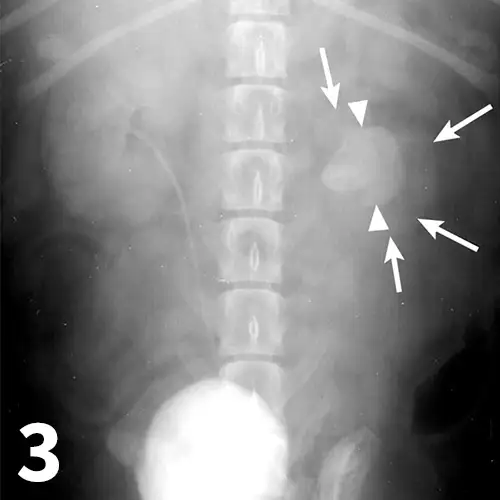

Survey abdominal radiographs (Figures 1 and 2) offer important information on kidney number, size, shape, symmetry, and location, as well as the presence of any mineralized opacities (eg, calcified tissue, nephroliths). The utility of abdominal radiographs is decreased in patients with abdominal fluid or lack of abdominal fat (eg, young or emaciated patients) because of lack of contrast. Excretory urography (IV pyelography), although more invasive, can augment survey radiographs and provide information about renal parenchymal architecture (eg, filling defects associated with cysts or infiltrative disease), the renal pelvis, and ureters as well as a qualitative assessment of global and individual renal excretory function (Figure 3).

Figure 1.

An enlarged left kidney with an irregular shape (arrows) is noted on the VD view of a dog with renal adenocarcinoma. The left kidney measured 4.5 times the length of L2; normal kidney length in the dog is 2.5 to 3.5 times the length of L2.